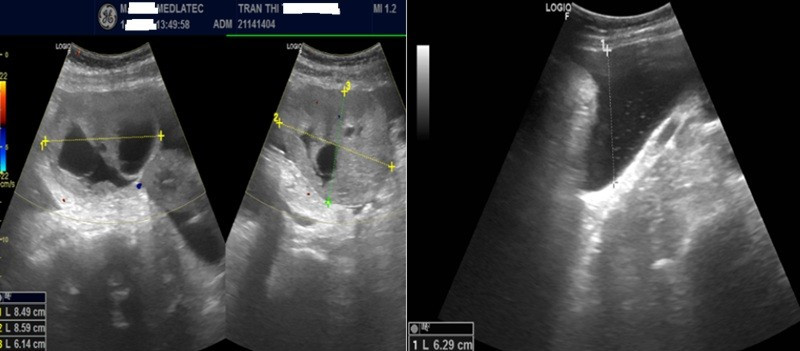

Kết quả, xét nghiệm dấu ấn ung thư thấy nồng độ CA 125 tăng cao ở mức 399 U/mL (giá trị bình thường 0–35) và HE4 là 469 pmol/L (bình thường <60,5). Siêu âm ghi nhận, hình ảnh khối hỗn hợp âm vùng tiểu khung, theo dõi u buồng trứng trái kèm dịch tự do ổ bụng.

Hình ảnh siêu âm ổ bụng của bệnh nhân/Ảnh Medlatec

Trên phim chụp cộng hưởng từ (MRI), phát hiện khối cạnh trái tử cung, nhiều dịch tự do ổ bụng, được phân loại O-RADS 5 – nhóm nguy cơ ác tính cao, đồng thời ghi nhận thêm khối vùng cổ tử cung.